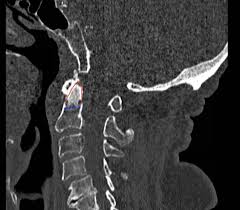

The transverse foramen is an opening on each of the transverse processes of the cervical spine which gives passage to the vertebral artery and vein and a sympathetic nerve plexus. There are two transverse processes that extend off each vertebra in the details: Transverse process fractures are common sequelae of trauma, although they are considered a minor and stable lumbar spine fracture. Transverse processes are typically fractured in direct blows from athletics touch or impact from falls from bikes/motorbikes or by heights. However, postmortem computed tomography (pmct) has made detection of this type of injury easy. There are two transverse processes that extend off each vertebra in the spine, one on each side. A transverse process fracture is a break in 1 or more transverse process. In 78% of transverse process fractures, ct scanning showed that the fracture extended into the transverse foramen. A transverse process fracture is considered as a rare injury. A transverse process fracture is a break in 1 or more transverse process. What is a transverse process fracture? Transverse process fractures caused by stress are likely under detected since even an acute transverse process fracture requires a high index of suspicion to be correctly identified(4,7). If ct confirms isolated injury lateral flexion/extension views are indicated to rule out dynamic instability.

However, postmortem computed tomography (pmct) has made detection of this type of injury easy. There are two transverse processes that extend off each vertebra in the details: What is a transverse process fracture? It may occur as an avulsion fracture due to strong contracture of the muscles. It occurs as a result of sudden and extreme trauma. If ct confirms isolated injury lateral flexion/extension views are indicated to rule out dynamic instability. Vertebral angiography, performed in eight patients with fractures involving the transverse foramen, showed dissection or occlusion of the vertebral artery in seven (88%) instances. This part extends out from the side of the main body of the bone (called the vertebral body). A transverse process fracture at the level of l5 is a surrogate marker of vertical instability of the pelvic fracture due to the attachment of the iliolumbar ligaments. We retrospectively reviewed the reports of lumbar spine and abdominopelvic ct scans from 2017 and 2018 to classify the types of spine fractures, their mechanism of injury, treatment and. Up to 60% of lumbar transverse process fractures identified on ct will be missed on plain radiographs. In 78% of transverse process fractures, ct scanning showed that the fracture extended into the transverse foramen. Transverse process fractures identified on helical computed tomography (ct) scans without the presence of any other fracture or.